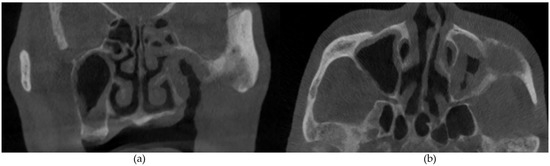

Figure 5. (a) Coronal and (b) axial sections demonstrating left maxillary sinus mucosal thickening. Extensive bony destruction of the maxillary alveolus, maxillary sinus walls, and zygoma can also be observed.